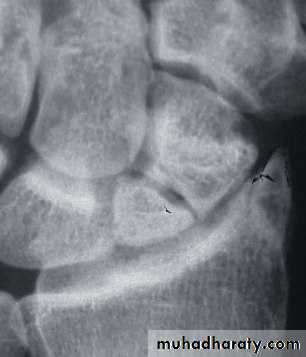

Usually the fracture is transverse and through the narrowest part of the bone (the waist) , but it could be in the proximal pole or in the tubercle ; few weeks after injury the fracture will be more obvious.

If union is delayed , cavitation appear on either side of the fracture .

In old ununited fracture there will be sclerosis at the edge and the appearance will be as there is extra carpal bone .Sclerosis of the proximal fragment is path gnomonic of avascular necrosis of the proximal fragment .